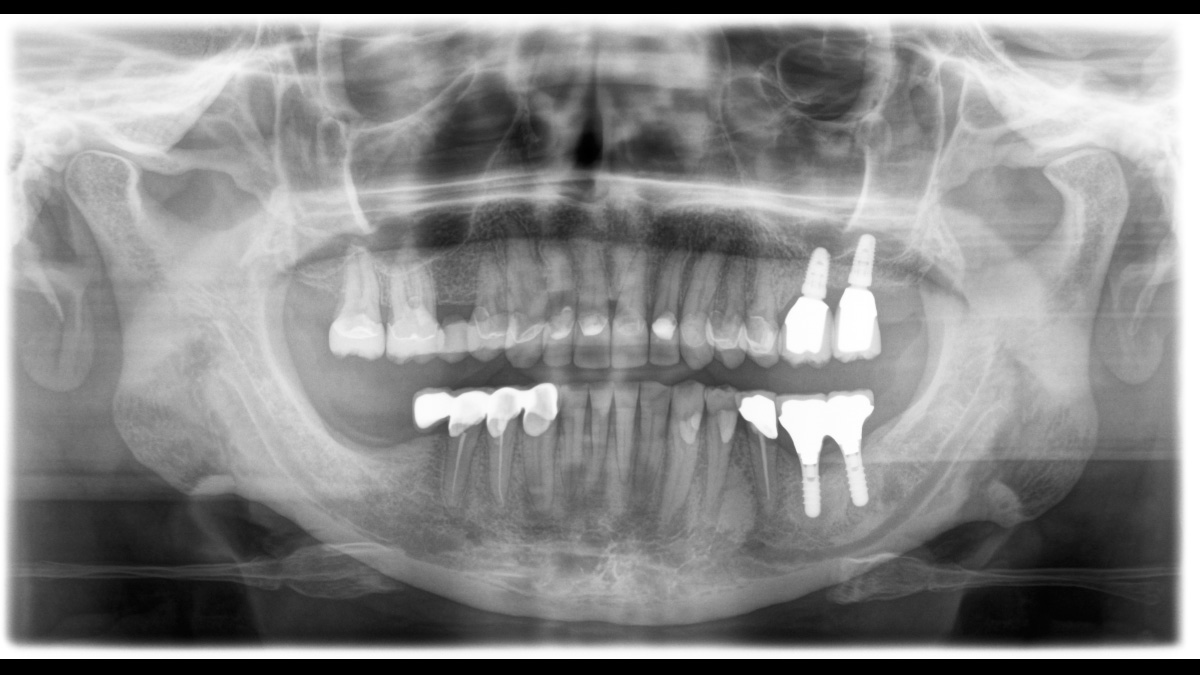

El enfoque correcto es crucial para excelentes radiografías panorámicas. Con la función de autofoco, usted recibirá automáticamente una imagen con la mejor nitidez posible en foco. Los dispositivos de radiología de Dentsply Sirona toman varios miles de imágenes individuales en un ciclo e identifican automáticamente las áreas donde la mandíbula está posicionada de manera óptima. Luego, sin ningún paso manual adicional, estas imágenes se muestran en una nítida imagen final.

Solo algunas partes de la imagen están en foco, mientras que otras áreas están borrosas.

El sistema detecta las áreas relevantes a partir de varios miles de imágenes individuales en un ciclo e identifica automáticamente las áreas donde la mandíbula está posicionada de manera óptima.

Imágenes nítidas.